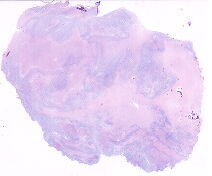

男, 50岁, 男,50岁,体检发现胰腺占位,手术剔除肿瘤送检,肉眼检查见结... |